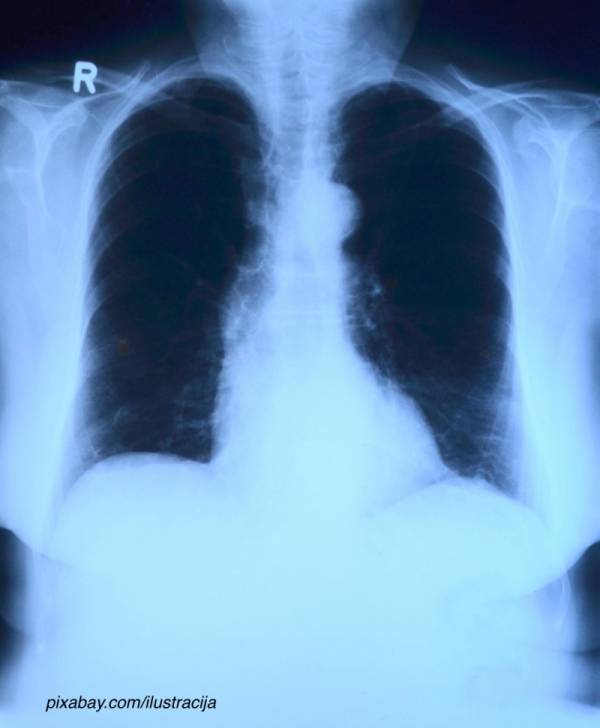

Grip je akutno virusno oboljenje respiratornog trakta, a najčešći simptomi su visoka telesna temperatura, glavobolja, bolovi u mišićima i zglobovima, bol u grlu i kašalj.